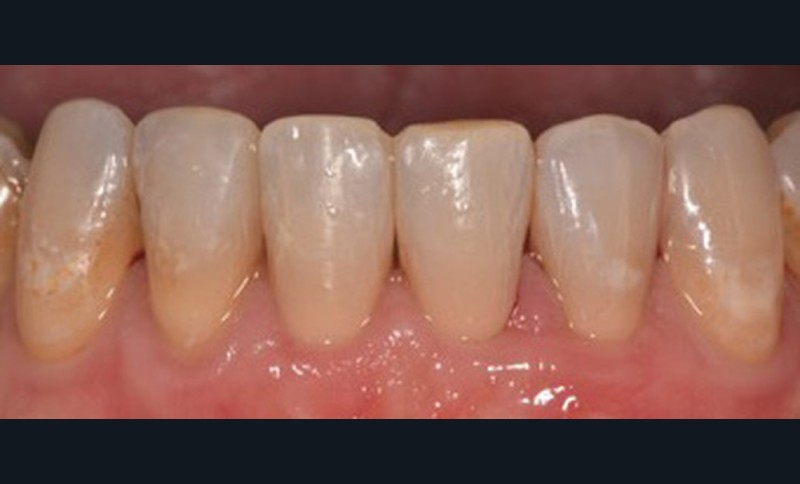

C’est à ces questions que nous permettront de répondre les deux premiers conférenciers, parodontologistes : le Dr Béatrice Straub nous présentera le renfort parodontal minéralisé, technique qu’elle a développée et pratique depuis de nombreuses années, pour éviter les préjudices des mouvements orthodontiques à risque, notamment lors des décompensations préchirurgicales (fig. 1a-d) ; le Pr Anton Sculean abordera le thème des greffes, avec leurs indications, les différentes techniques à privilégier et illustrera ses propos par de nombreux cas cliniques aux résultats esthétiques impressionnants.

Professeur et chef de service du département de parodontologie et actuellement directeur opérationnel de l’école de médecine dentaire de l’université de Berne, en Suisse, le Pr Sculean est actuellement répertorié comme l’expert le mieux coté en parodontologie dans le monde1. Il est l’auteur du livre Periodontal regenerative therapy consacré aux techniques régénératives contemporaines dans le traitement des défauts osseux et des tissus. Par sa compréhension de l’anatomie du parodonte et des phénomènes de cicatrisation biologique des plaies, sa maîtrise des matériaux régénératifs et des techniques chirurgicales, il nous propose des paradigmes de traitement efficaces et prédictibles. L’objectif est de donner un aperçu des possibilités et des limites de la couverture des récessions en prévention avant ou après un traitement orthodontique. L’utilisation de techniques de greffes tunnelisées permet une couverture prévisible et une augmentation de l’épaisseur des tissus pour les récessions gingivales simples et multiples, tout en assurant une stabilité à long terme. Anton Sculean nous propose une approche clinique rigoureuse et efficace, richement illustrée, qui renouvelle notre collaboration interdisciplinaire avec la parodontologie. Un rendez-vous à ne pas manquer !